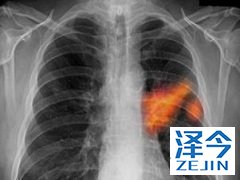

布加替尼针对脑复发的ALK患者有治疗效果 目前临床上采用靶向治疗方法对ALK阳性的肺癌患者进行治疗,并且已经取得了进展。不过一些患者在治疗之后会出现复发情况,并且是在大脑这个比较复杂的部位。克唑替尼是针对发生脑转移之前的靶向药物,但是出现发生转移的患者使用克唑替尼的效果却微乎其微,这时能够使用布加替尼进行治疗吗?

布加替尼(AP26113)是一种新型高选择性和有效的ALK和ROS1抑制剂,具有高度选择性。在体外,与克唑替尼相比,布加替尼不仅抑制ALK,效力提高12倍,而且抑制IGF-1R,FLT3和EGFR突变体,具有抗EGFR T790M抗性突变的一些活性。在异种移植模型中,布加替尼克服了对ALK抑制剂的耐药性,包括对第一代和第二代抑制剂具有抗性的ALK G1202R突变。布利沙替尼对克唑替尼耐药,ALK的疗效阳性患者已经在两项早期研究中得到证实,这导致其在这种情况下获得批准,并且目前正在研究作为酪氨酸激酶抑制剂初治患者中的克唑替尼的一线治疗。

布加替尼不仅表现出有希望的全身活动,而且在克唑替尼耐药人群中的客观缓解率和无进展生存率方面也显着改善了颅内结果,最佳疗效为180 mg(运行90 mg后)在7天内)和良好的耐受性。这些数据证实,在克唑替尼治疗失败后,布加替尼是一种很好的治疗策略,特别是在中枢神经系统受累的情况下。

布加替尼对于晚期的NSCLC患者的治疗,特别是对于克唑替尼产生耐药的患者,有着明显的治疗效果,患者可以在医生的指导下进行选择用药,您也可以咨询上海泽今健康获取相关帮助。